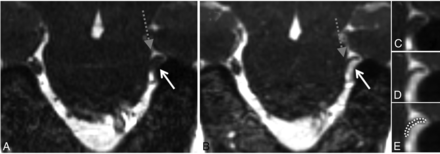

Grades 0 and 1 neurovascular conflict. Coronal NE-CISS (A) and CE-CISS (B) images show grade 1 (simple contact) on the patient's right side with a branch from the superior cerebellar artery (white solid arrow) contacting the cisternal segment of the trigeminal nerve root (dashed black arrow) from above. Note enhancement of the artery on the CE-CISS image. On the patient's left, the cisternal trigeminal nerve root (dashed black arrow) has no neurovascular conflict (grade 0).